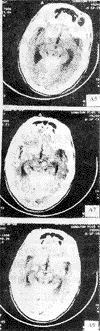

人脑CT(示四叠体)